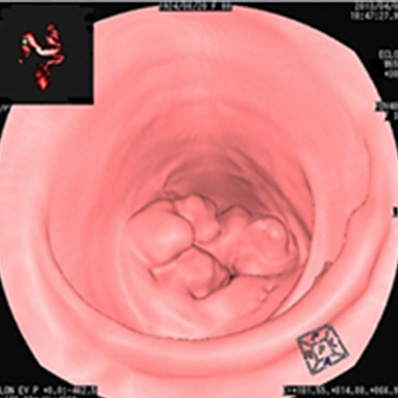

早期大腸癌

内視鏡で発見しました。

その場で切除しました。